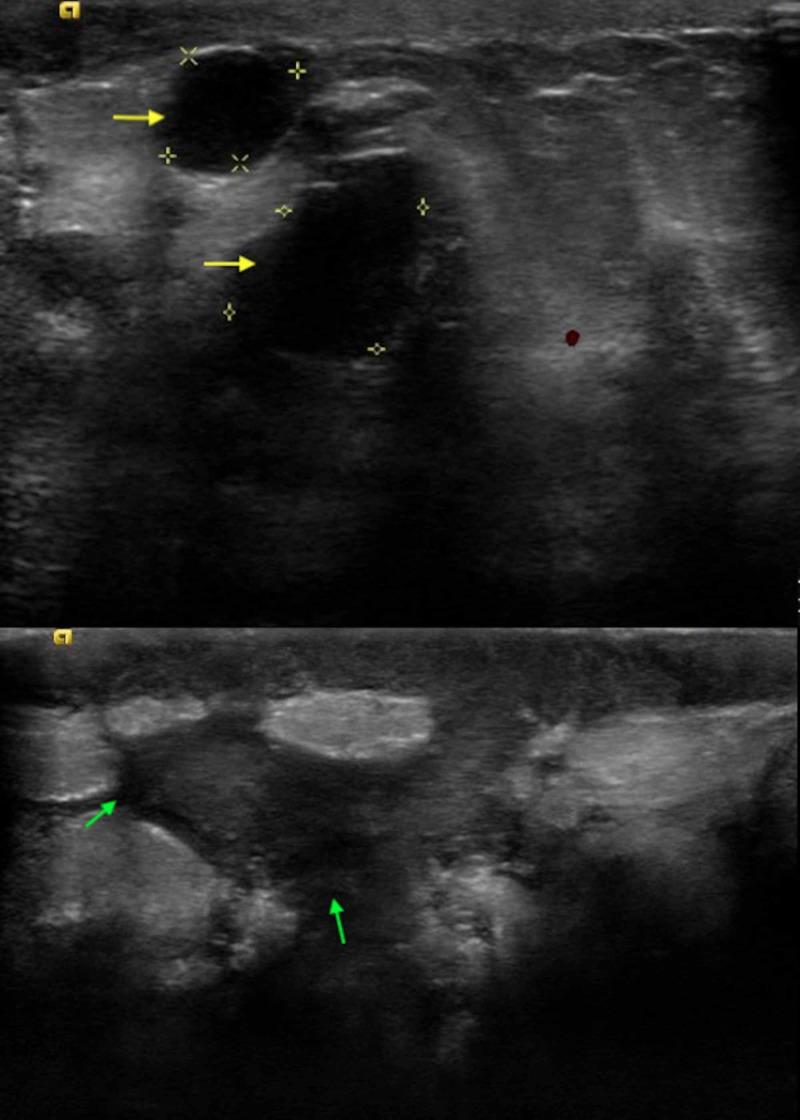

Idiopathic granulomatous mastitis (IGM) is a rare, benign, and chronic inflammatory condition of the breast. Women of child-bearing age with a recent history of pregnancy and lactation are usually affected, and clinical picture mimics inflammatory breast cancer or breast abscess. The etiology is not well defined but proposed to be a localized immune reaction to the breast tissue. Here, we report a case of a 41-year-old female who presented with left breast pain and discharge and a clinical diagnosis of breast abscess was made. No improvement with antibiotics was noted and she underwent mammography and diagnostic ultrasound of the affected breast. A biopsy of the lesion was obtained which revealed chronic granulomatous inflammation confirming the diagnosis of IGM. She was also found to have hyperprolactinemia secondary to a prolactinoma following which the patient was started on steroid and bromocriptine.

摘要

特发性肉芽肿性乳腺炎(IGM)是一种罕见的、良性的乳腺慢性炎症性疾病。育龄期近期有妊娠和哺乳史的女性通常会受到影响,其临床表现类似炎性乳腺癌或乳腺脓肿。病因尚不明确,但推测是对乳腺组织的局部免疫反应。在此,我们报告一例41岁女性,她因左乳疼痛和溢液就诊,临床诊断为乳腺脓肿。使用抗生素治疗后未见改善,遂对患侧乳房进行了乳腺钼靶检查和诊断性超声检查。对病变进行活检,结果显示为慢性肉芽肿性炎症,确诊为IGM。还发现她因泌乳素瘤继发高泌乳素血症,随后患者开始接受类固醇和溴隐亭治疗。